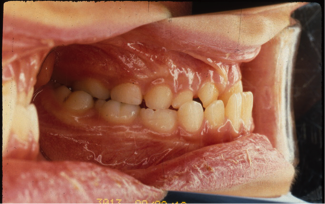

外科矯正治療(はんたいこうごう)

21歳/女性

悩み:顎の曲がりと下顎のでっぱり

下の顎が変形し、上の歯が下の歯より前に出ている状態

治療期間:約2年

治療前

治療後

矯正治療と外科手術を併用して行った患者さんです。

「早い治療計画」での依頼のため、歯を抜かずに矯正治療を10ヶ月行い手術という事になりました。

その後6ヶ月の術後矯正にて終了となりました。

手術も含めて早期治療が目的の患者さんでしたので満足されてよかったです。